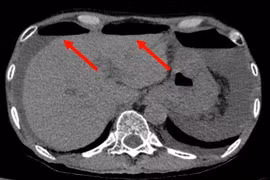

(khoahocdoisong.vn) - Bệnh về đường tiêu hóa hết sức đa dạng như viêm loét dạ dày tá tràng, trào ngược dạ dày thực quản, viêm đại tràng, trong đó, nguy hiểm hơn là bệnh ung thư đại trực tràng - bệnh rất phổ biến tại Việt Nam và trên thế giới.